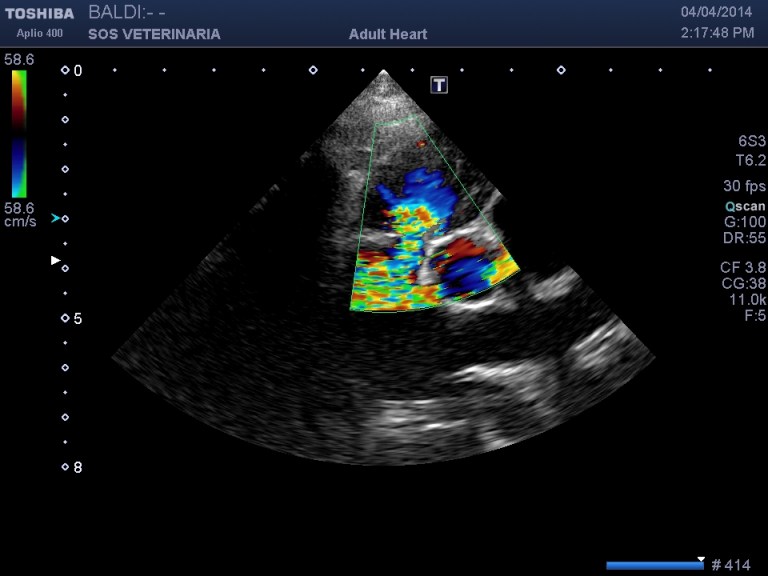

parasternale desta asse corto

Anatomicamente la stenosi polmonare può essere classificata come sopravalvolare, valvolare, sottovalvolare. Di queste tre forme la stenosi polmonare valvolare è quella più frequente e può essere a sua volta suddivisa in due fenotipi: tipo A (anulus normale , doming dei lembi valvolari e dilatazione poststenotica) )e tipo B. (anulus ipoplastico ,lembi rudimentali ,assenza di dilatazione post)

Nel buldog inglese ma anche in altre razze (es Boxer) la stenosi polmonare puo’ essere provocata da una anomalia coronarica che genera una forma di stenosi sottovalvolare .E’ importante riconoscere tale anomalia in quanto il trattamento di valvuloplastica non solo e’ inutile ma anche controindicato per il rischio di morte (ischemia e avulsione della coronaria)

In questa malformazione, una grande arteria coronaria singola origina dal seno aortico coronario di destra dividendosi subito nelle branche di destra e sinistra. L’arteria coronaria principale di sinistra circonda e comprime il tratto d’efflusso ventricolare destro appena sotto la valvola polmonare, prima di dividersi nelle arterie coronarie discendente di sinistra e circonflessa di sinistra.

Nella visione delle immagini e dei filmati richiamo l’attenzione ad alcuni criteri di semplice reperibilita’ che portano la diagnosi verso questa anomalia :

- imponente il grado di ipertrofia concentrica ventricolare destra con gradienti molto elevati superiori ai 100 mmHg (anche 160mmHg),il cuore ha subito fin da subito un necessario rimodellamento alla condizione

- L’anello stenotico e’ sempre piccolo

- difficilmente si visualizzano i lembi valvolari in quanto il restringimento dell’anulus generato dal passaggio della coronaria impedisce la loro apertura ,in transtoracica si possono visualizzare dritti come canne al vento

- nelle scansioni in cui si intravedono i lembi valvolari nessun effetto doming appare visualizzabile( come nella stenosi polmonare classica di tipo A)

- invece di lembi valvolari si visualizza un cordoncino simil fibroso il diametro della stenosi e’ sempre piccolo